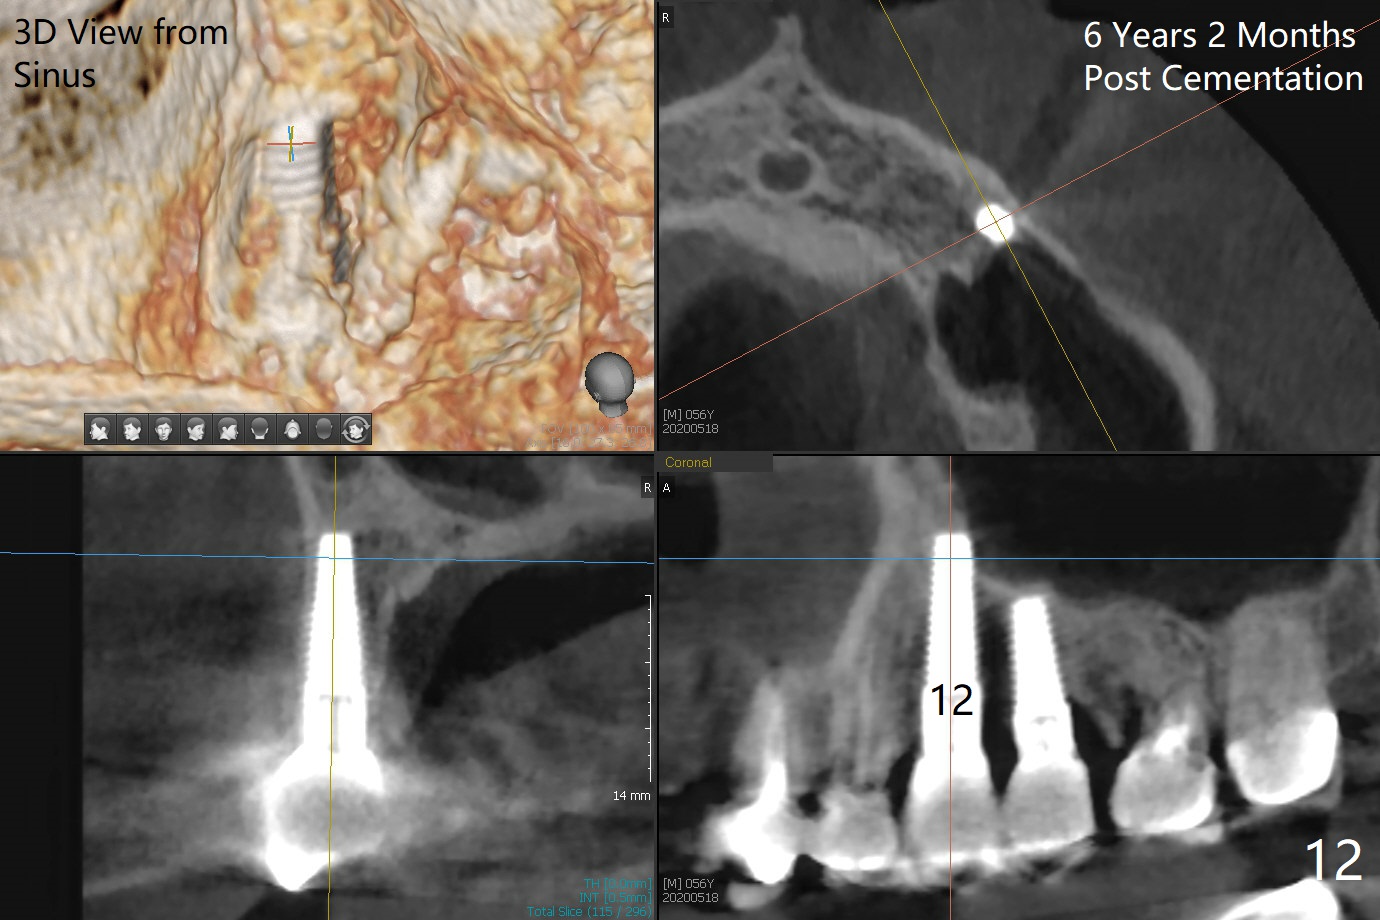

A 50-year-old man has mild pain in the upper left 1st bicuspid 3 years after root canal retreatment with placement of two posts (Fig.1). Findings of clinical exam are consistent with root fracture (Fig.2). Extraction reveals two fused roots (Fig.3,4). Probing indicates that the buccal plate is defective. Osteotomy is initiated in the palatal socket with a 2 mm pilot drill, followed by 2.5 and 3.0 mm reamers and 4.5x20 mm tap. The septum appears to have been pushed buccally (Fig.5 *) and form a new buccal wall (partially, strengthened by bone graft mentioned below) for the implant to be placed. The implant (4.5x20 mm) is placed in the palatal socket (Fig.6 *) with insertion of an abutment (A: 3.5x5 mm 0º), while a mixture of autogenous bone (harvested from reamers) and Synthograft (Bicon) is placed in the shrunken buccal socket (Fig.7; using allograft may decrease postop bony shrinkage). The bone graft is then contained by an immediate provisonal without collagen membrane or flaps. The patient is doing well postop. The gingiva is healthy (Fig.8*) when the provisional is removed 3 months postop with normal papillae (Fig.9 arrowheads). It remains the same 1 month post cementation (Fig.10,11). For further follow up, see immediate implant of the tooth #13.